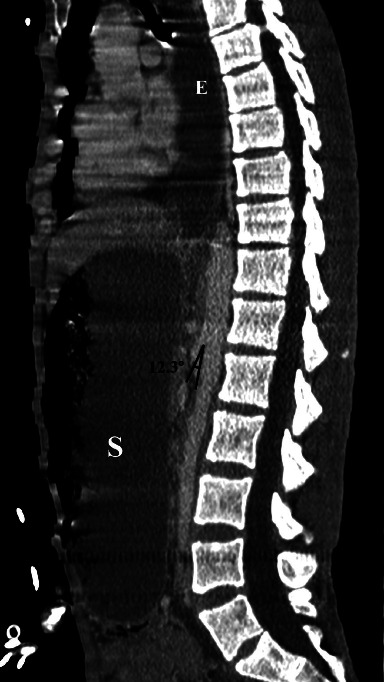

肠系膜上动脉综合征(SMAS)是一种罕见的不寻常疾病,经临床怀疑和放射学证实。由于腹腔内脂肪减少,十二指肠第三部分与腹主动脉(AA)和肠系膜上动脉(SMA)之间发生撞击,继发十二指肠梗阻。高发病率和高死亡率与漏诊或晚诊有关,而漏诊或晚诊可导致胃穿孔和胃出血等并发症。我们介绍了一例 33 岁的男性病例,他以前并不知道自己患有 SMAS,因出现脓毒性休克症状而到急诊科就诊,主诉发烧和呼吸道症状持续数天。检查结果显示,吸入性肺炎继发于上消化道梗阻,计算机断层扫描(CT)显示有 SMAS 征象。病情急剧恶化导致心脏骤停并死亡。通过这篇文章,我们强调了早期正确诊断 SMAS 的重要性,因为没有一个数字是严格意义上的诊断,必须根据临床病史和体格检查来解释放射图像,所以诊断 SMAS 有时很困难。

Superior mesenteric artery syndrome (SMAS) is a rare and unusual disease, suspected clinically and confirmed radiologically. It represents a duodenal obstruction secondary to the impingement of the third portion of the duodenum between the abdominal aorta (AA) and the superior mesenteric artery (SMA) due to decreased intraabdominal fat. High morbidity and mortality rates are linked to missed or late diagnosis that can lead to complications, such as gastric perforation and gastric hemorrhage. We present the case of a 33-year-old man who was not previously known to have a SMAS, who presented to the emergency department with signs of septic shock, complaining of fever and respiratory symptoms for several days. Investigations showed aspiration pneumonia secondary to an upper gastrointestinal obstruction with signs of SMAS on a computed tomography (CT) scanner. Acute and rapid deterioration led to cardiac arrest and death. Through this article, we highlight the importance of early and correct diagnosis of SMAS which can sometimes be challenging, since no number is strictly diagnostic and radiological images must be interpreted in light of the clinical history and physical examination.